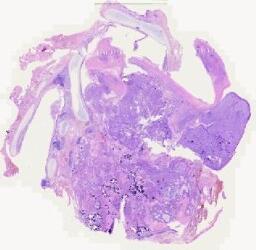

临床资料: 患者女65岁,呼吸困难,外院诊断胸腔积液,行胸腔闭式引流并给抗炎溶栓对症治疗未见好转。现形成包裹性积液,胸膜黏连,为求进一步治疗来我院。术中探查见胸腔黏连,包裹胸水,胸膜广泛增厚,前上胸壁胸膜肿物明显,术中取部分肿物送病理。